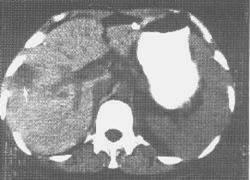

肝结核(tuberculosis of the liver)较为少见,因缺乏特异的症状和体征,故临床误诊误治率较高。多数肝结核系全身粟粒性结核的一部分,称为继发性肝结核,患者主要表现为肝外肺、肠等结核引起的临床表现,一般不出现肝病的临床症状,经过抗结核治疗肝内结核可随之治愈,临床上很难作出肝结核的诊断。原发性肝结核系指结核累及肝脏,并成为其全部临床表现的原因,或者当发生肝结核时,其他部位的结核病灶已自愈或非常隐匿而未发现,肝脏为唯一发现结核的器官。此时,患者有结核病的全身表现和/或肝病的局部表现,如发热、畏寒、盗汗、乏力、消瘦、恶心、呕吐、腹胀、腹泻、肝区疼痛及触痛、肝肿大及黄疸等。